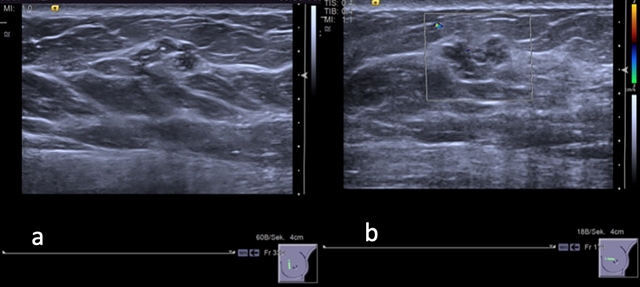

(a) 灰度超声图像显示左乳内乳晕旁区域有低回声“肿块”病变,边缘呈分叶状且部分边界不清;(b) 彩色多普勒图像显示病变周围无血管分布。

本研究的目的是根据临床、病理学和放射学数据从外部验证 B3 乳腺病变风险分层评分的可行性和稳健性,以改进临床决策。本研究通过回顾性研究纳入了经本院超声引导下活检诊断出的129例组织学证实的B3病变。患者和病变相关变量由两名不知情的乳腺放射科医师 (R1、R2) 独立评估,为每个特征分配从0到2的分数 (最高总分为5)。在两个不同的阈值 (≥1和2) 下计算灵敏度、特异性、阳性和阴性预测值。使用卡方检验和费歇尔精确检验比较分类变量。通过ROC分析评估了区分良性和恶性B3病变的评分的诊断准确性。结果显示对117/129 (90.6%)个病变进行了手术,这117个病变中有11 (9.4%) 个是恶性的。在至少24个月的随访中未发现癌症。ROC曲线下的面积为 0.736 (R1) 至 0.747 (R2),两名医师之间没有显着差异 (p = 0.5015)。使用≥1的阈值,灵敏度、特异性、阳性预测值和阴性预测值分别为90%/90% (R1/R2)、39%/38% (R1/R2)、11%/12% (R1/R2) 和97%/98% (R1/R2)。两名医师对47个评分≤1的病变 (相关恶性肿瘤风险低) 进行了分类。其中,只有一个恶性病变未得到充分诊断 (乳腺导管内原位癌-G1)。结论证明在外部验证中,该评分显示出较高的阴性预测值,并且有可能将超声检测到的 B3 病变的不必要的手术或再活检减少达39%。